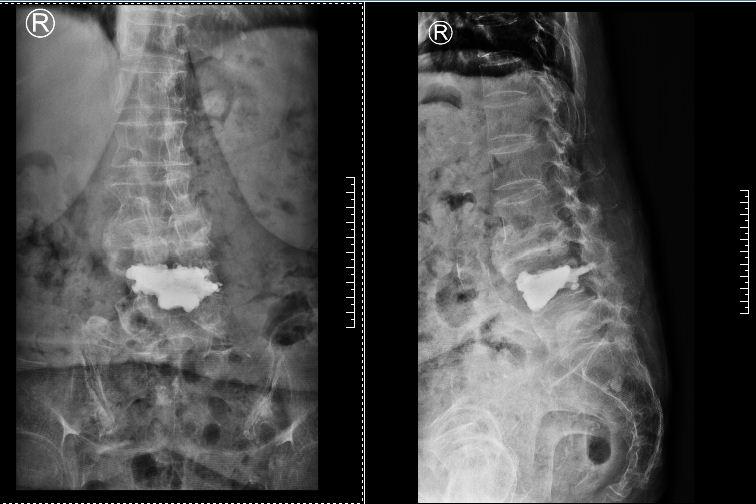

▲術后磁共振、X片

經過進一步康復治療,又過了兩天,張奶奶已經可以獨自下地走路了,如同重獲新生。她對曾小軍的技術贊不絕口,對醫(yī)護人員的照顧感激不盡。